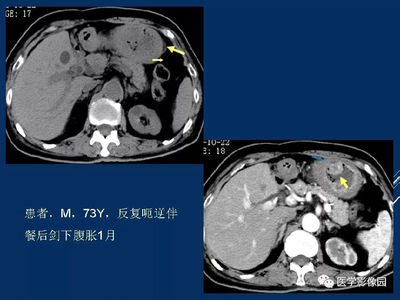

不是,只是怀疑,需要进一步诊断。那还是太片面了。一般还有其他指标可以参考。内镜(EUS)能清晰显示胃壁的五层结构,准确探查肿瘤的起源水平、体积、边界及回声模式。是目前诊断黏膜下肿瘤最准确的方法,也是术前诊断和评估间质瘤最有价值的手段。EUS超声显示:胃壁固有肌层低回声病变,回声略高于正常固有肌层;